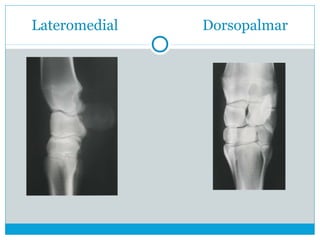

Dorsopalmar Lateromedial

 DorsoPalmar

 LateroMedial